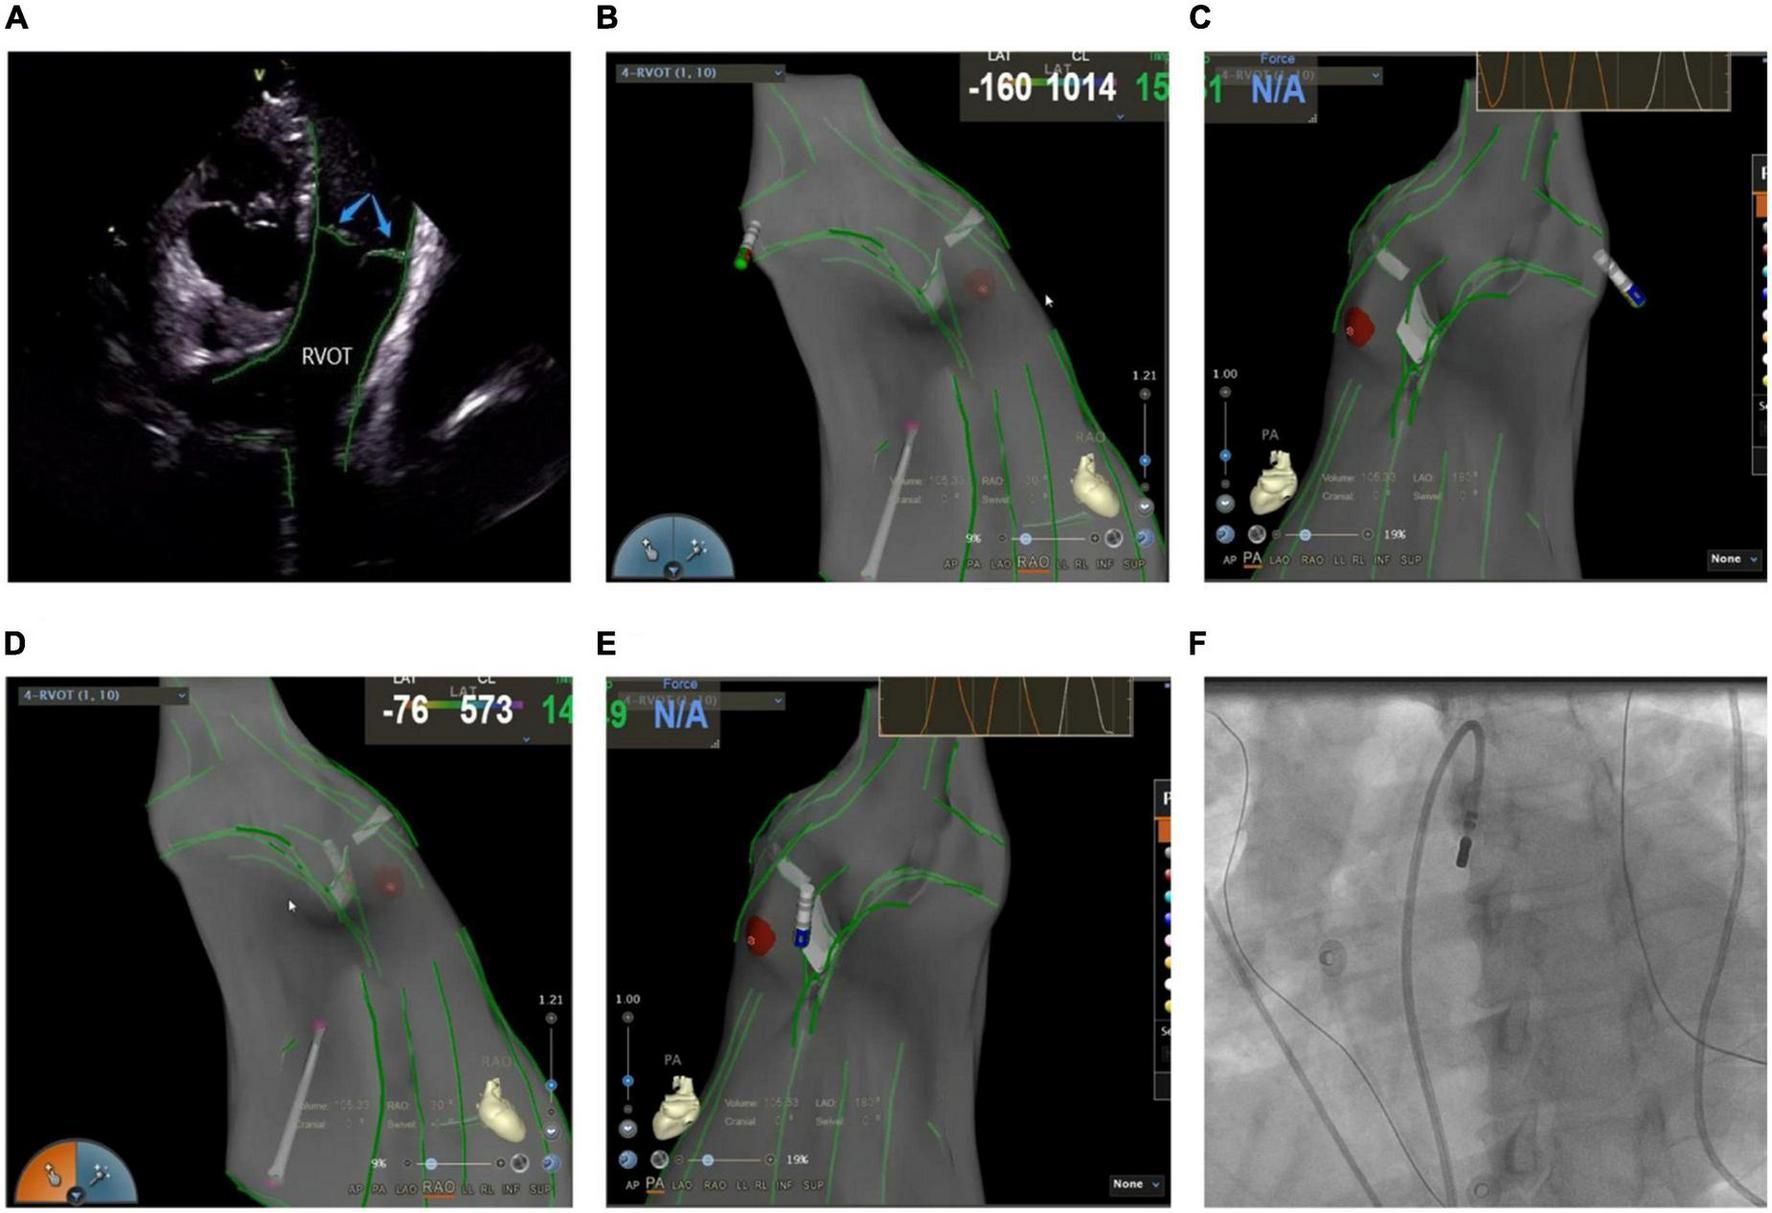

Mostly idiopathic, right ventricular outflow tract arrhythmias are the most common form of clinical ventricular arrhythmias, accounting for about 80% of the total outflow tract ventricular arrhythmias (18). The myocardial tissue of the RVOT anatomically extends to the pulmonary valve and the pulmonary artery, which makes the ablation target location more complex. A previous study suggested that about 90% of the subjects had myocardial extension above the pulmonary valve, whereas nearly half (46%) of the RVOT arrhythmia lesions were located above the pulmonary valve (19). In recent years, inverted U-shaped ablation above the pulmonary valve has been widely popularized due to an increased understanding of the RVOT ablation mechanism (20, 21). ICE technique shows the precise position and relationship between the ablation catheter, pulmonary valve, pulmonary artery, and RVOT defines the position of supra-and subvalvular reflexes, visualizes the adhesion and stability of the ablation catheter and the target tissue in real-time as well as monitors the occurrence of procedural complications like valve perforation (Figure 5). Due to the complex anatomy surrounding RVOT, radiofrequency energy transmitted near coronary arteries can lead to the occlusion of major epicardial vessels like the left anterior descending coronary artery, thereby causing myocardial infarction in some cases (22). Hence, it’s critical to identify the functional status of the coronary arteries. De Sensi et al. (23) and Ho (24) reported several successful cases of inverted U-shaped RVOT under the guidance of ICE. The pulmonary artery, aortic valve, left anterior descending branch, and RVOT were precisely monitored in real-time, thus, avoiding the use of radiography and contrast agents, with no perioperative complications.

FIGURE 5

(A) Anatomic reconstruction of right ventricular outflow tract under ICE. RVOT: right ventricular outflow tract; Blue arrow: pulmonary valve. (B,C) Image of the catheter successfully entering the pulmonary artery under the CARTOSOUND module. (B) Right anterior oblique view; (C) pulmonary artery view. (D,E) Image of the catheter successfully attached to the pulmonary sinus in a reverse U-shape under the CARTOSOUND module. (D) Right anterior oblique view; (E) pulmonary artery view. (F) Successful placement of the catheter above the pulmonary sinus was verified by angiography.